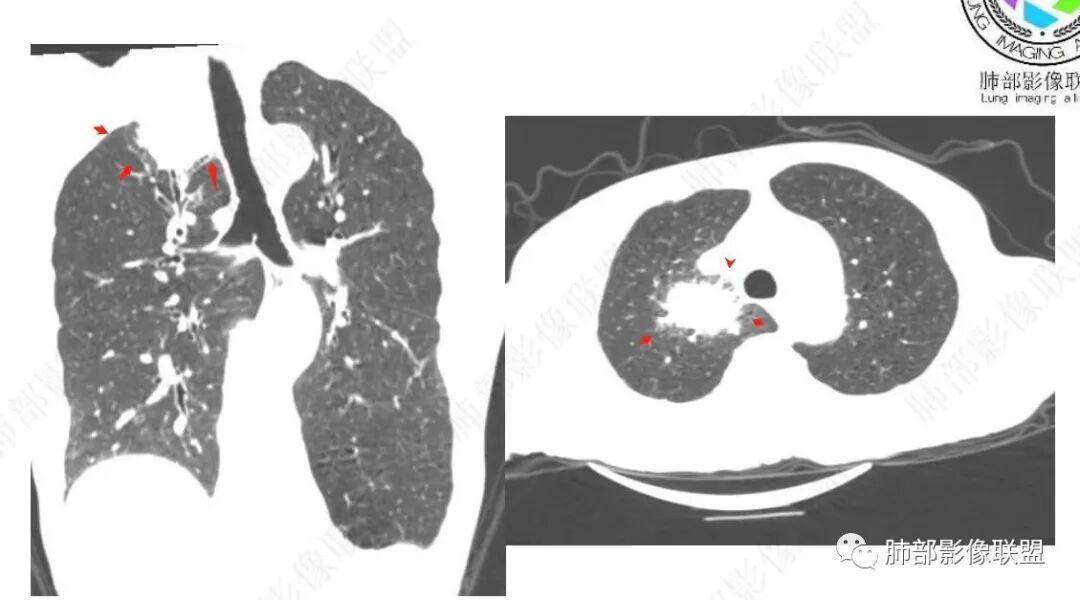

老年人,有高血压、脑梗死、肾结石病史

右下叶背段有结节

主病灶在右上叶尖段、前段纵隔旁,紧贴胸膜

楔形、边缘膨隆,附近见斑片状、网格状高密度影

支气管近端堵塞,可惜显示的不一定全面

支气管壁还是弥漫增厚

中央坏死明确

整体内壁偏清楚,似乎有些地方欠清,不知道是否厚层所致

整体而言:远侧、内侧壁厚

患者有高血压、脑梗死、肾结石病史,因左胸痛不适入院,伴高热,血常规示白细胞、中性粒细胞高。胸部CT示右肺上叶肿块影,边缘模糊影,内可见低密度坏死,边界清楚,一月后出现气液平面,周围渗出,治疗2周复查液平及周围炎症吸收,肿块未见明显吸收。

考虑肿瘤?右肺上叶高密度影,边缘模糊,侵及纵隔及胸廓入口,病灶密度不均匀,部分支气管截断,增强后不均匀强化,内可见较大范围坏死,纵隔多发肿大淋巴结不均匀强化。肺上沟瘤不能排除。

感染性病变?右肺上叶尖段团块影,中央见大片状状坏死伴液气平面,周围见斑片状高密度影,实验室检查血象明显升高,抗炎治疗后,病灶有所吸收缩小,灶周斑片状消失。